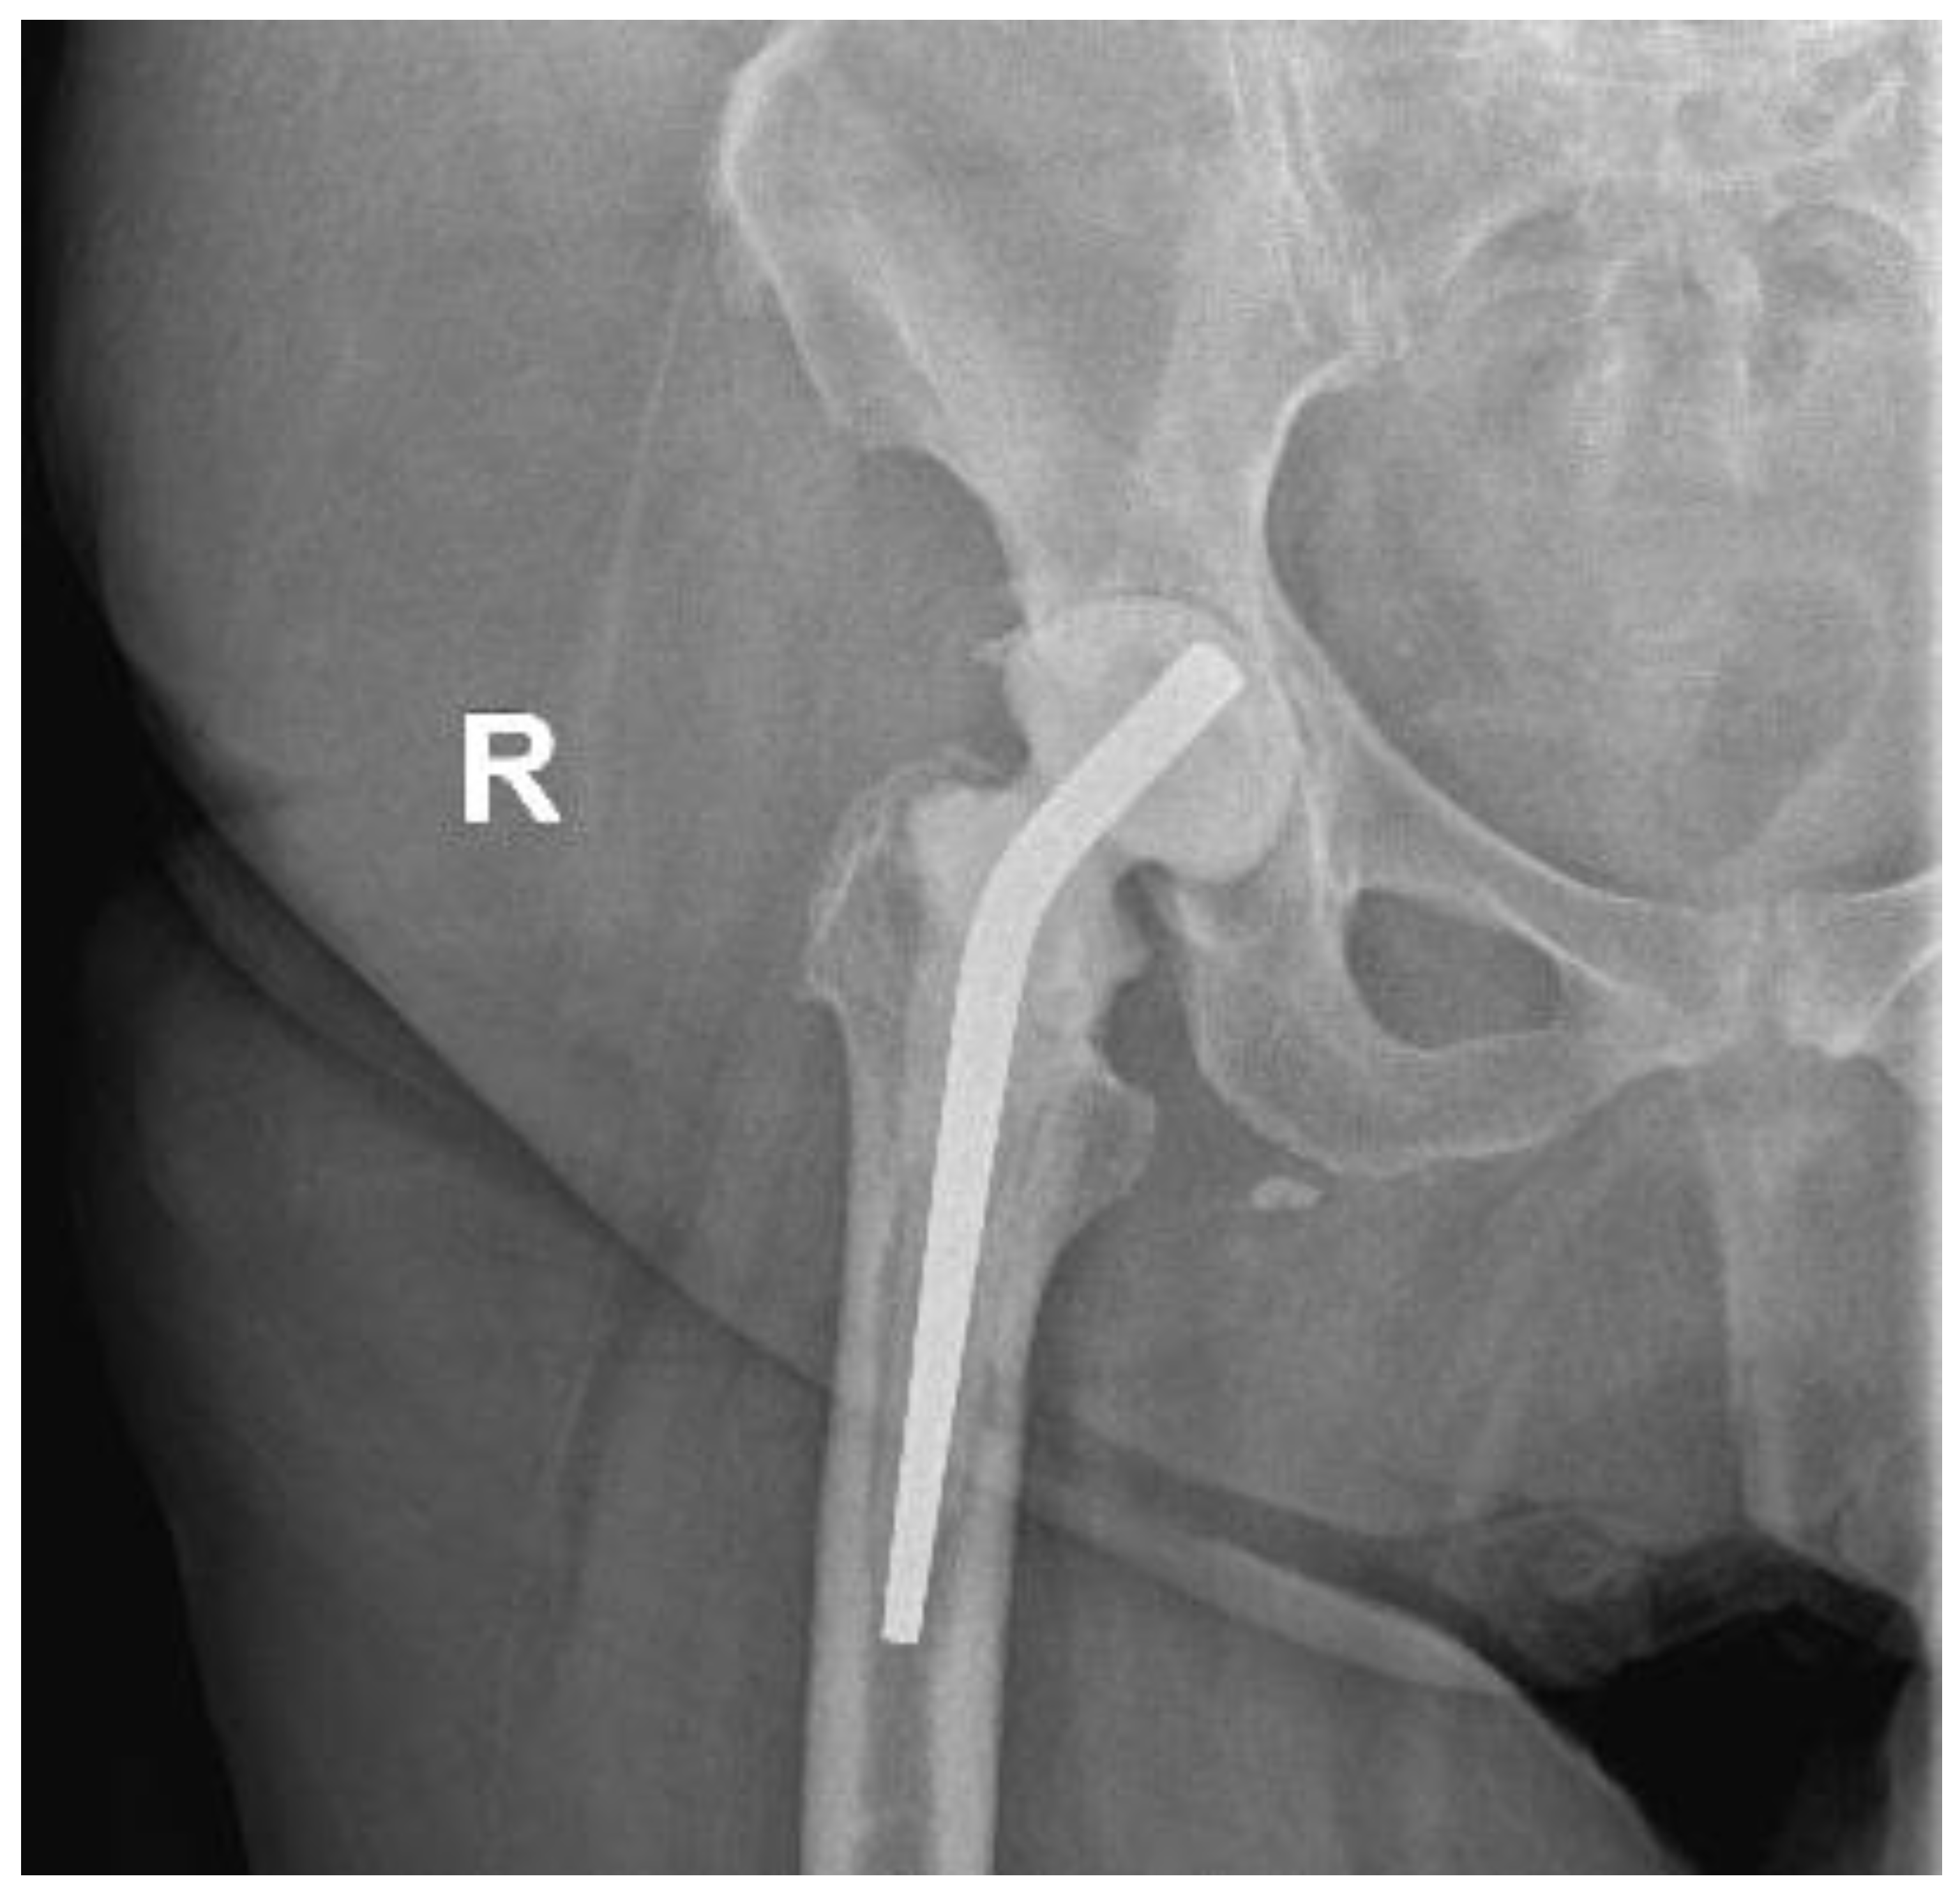

Regarding her orthopaedic medical history, four years previously, the patient underwent a right THA at a private institution through a standard Anterior Minimally Invasive Surgery (AMIS) approach (Figure 1). From the first postoperative days, serous wound drainage was discerned. Following that, she was reoperated on twice at the same hospital and by the same team, thirty days and forty-five days after the initial surgery, where wound exploration, debridement and washout with implant retention were performed due to residual pain and incessant wound leakage. Subsequently, the AMIS wound was not entirely healed, and the patient continued to complain about wound drainage and hip pain. She was discharged home with vacuum-assisted wound closure (VAC) and per os antibiotics. Finally, successful wound healing was achieved roughly four months after the primary THA.

Figure 1. Pelvis X-ray on admission date.